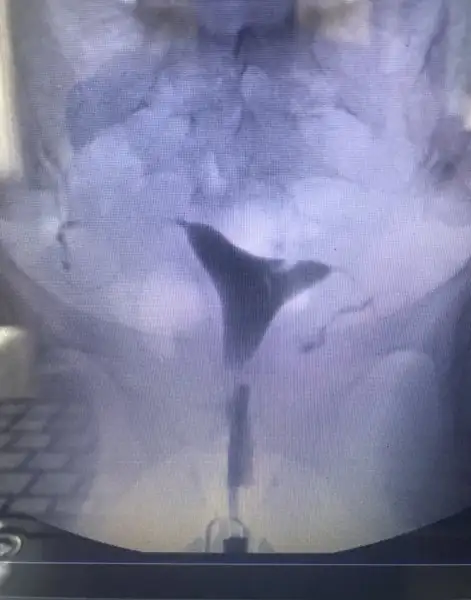

Aslında raporu alsam daha net olacak ama işte 1 haftaya çıkar ded bide acıbadem :) şişlikten bahsetmemişti doktor ama bilemedim şimdiHidroselpinks görüntüsü var gibi fotolarda ilerledikçe şişmeye başlamış sanki her iki tüpte de mevcut ama o kadar ileri düzeyde değil hidroselpinks

Şişlik dediğim fotoda ilerleyince oluşan beyaz görüntü varya sağda ve solda ondan bahsediyorum

Hidroselpinks deniliyor ona tüplerde tıkanıklık sonucu oluşan sıvının rahime sızıntı şeklinde akması iltihap yani

Ben anestezili çekildiğim için acıyı hissetmedim ama benimde gördüğüm kadarıyla ilaç iki tarafa da ulaşmış. Sizin filmde buna mı benziyrodu? İyi düşünüyorum zaten inşallah iyi de olacak sonuç :)Ben cekilirken doktor iki tarafta da aci var mi demisti. Sonra cekince baktim sizinki gibi rahmin 2 yanina ilac ulasmis kanallarin tamamen açık dedi. Ben suan sizinki icin öyle düşündüm. Açıldi demis sonuçta tıkanıklık. Iyi dusunun iyi olsun

Açık gibi gözüküyor canım bende çektirdim benim sol kapalı sağ ucundan kapalı çıktı sen be kadara çektirdin acabakızlar selamlar rahim filmi görüntülerini ekliyorum bilgisi olan yardımcı olur mu?

Aynen kapalı olanlarda baya belli oluyor. Benim ilaç gitmiş gibi görünüyor. Anestezili 800 e çekilde benimkiAçık gibi gözüküyor canım bende çektirdim benim sol kapalı sağ ucundan kapalı çıktı sen be kadara çektirdin acaba